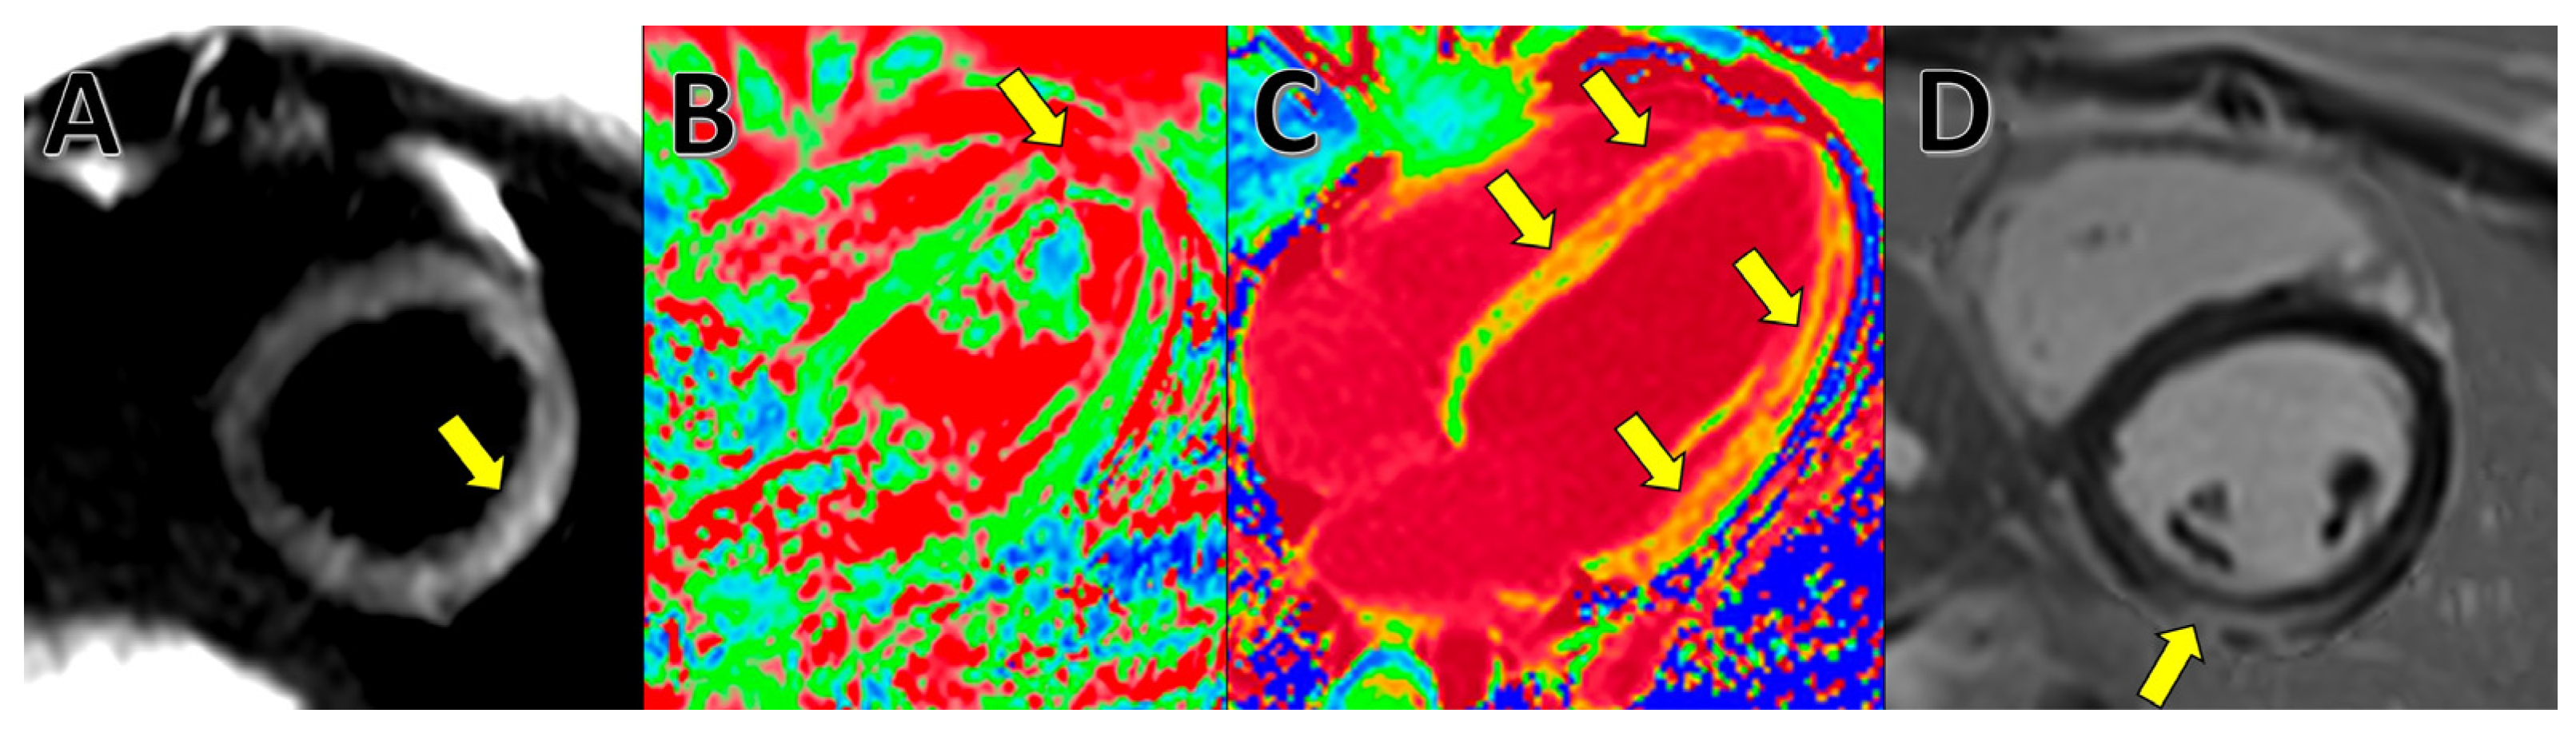

4. Cardiac Magnetic Resonance (CMR)

- Ferreira, V.M.; Schulz-Menger, J.; Holmvang, G.; Kramer, C.M.; Carbone, I.; Sechtem, U.; Kindermann, I.; Gutberlet, M.; Cooper, L.T.; Liu, P.; et al. Cardiovascular Magnetic Resonance in Nonischemic Myocardial Inflammation: Expert Recommendations. J. Am. Coll. Cardiol. 2018, 72, 3158–3176. [Google Scholar] [CrossRef] [PubMed]

- Kim, P.K.; Hong, Y.J.; Im, D.J.; Suh, Y.J.; Park, C.H.; Kim, J.Y.; Chang, S.; Lee, H.-J.; Hur, J.; Kim, Y.J.; et al. Myocardial T1 and T2 Mapping: Techniques and Clinical Applications. Korean J. Radiol. 2017, 18, 113. [Google Scholar] [CrossRef] [PubMed] [Green Version]

- Eitel, I.; Friedrich, M.G. T2-weighted cardiovascular magnetic resonance in acute cardiac disease. J. Cardiovasc. Magn. Reson. 2011, 13, 13. [Google Scholar] [CrossRef] [PubMed] [Green Version]

- O’Brien, A.T.; Gil, K.E.; Varghese, J.; Simonetti, O.P.; Zareba, K.M. T2 mapping in myocardial disease: A comprehensive review. J. Cardiovasc. Magn. Reson. 2022, 24, 33. [Google Scholar] [CrossRef] [PubMed]

- Kravchenko, D.; Isaak, A.; Mesropyan, N.; Bischoff, L.M.; Pieper, C.C.; Attenberger, U.; Kuetting, D.; Zimmer, S.; Hart, C.; Luetkens, J.A. Cardiac magnetic resonance follow-up of COVID-19 vaccine associated acute myocarditis. Front. Cardiovasc. Med. 2022, 9, 1049256. [Google Scholar] [CrossRef]

- Georgiopoulos, G.; Figliozzi, S.; Sanguineti, F.; Aquaro, G.D.; Di Bella, G.; Stamatelopoulos, K.; Chiribiri, A.; Garot, J.; Masci, P.G.; Ismail, T.F. Prognostic Impact of Late Gadolinium Enhancement by Cardiovascular Magnetic Resonance in Myocarditis: A Systematic Review and Meta-Analysis. Circ. Cardiovasc. Imaging 2021, 14, E011492. [Google Scholar] [CrossRef]

- Haaf, P.; Garg, P.; Messroghli, D.R.; Broadbent, D.A.; Greenwood, J.P.; Plein, S. Cardiac T1 Mapping and Extracellular Volume (ECV) in clinical practice: A comprehensive review. J. Cardiovasc. Magn. Reson. 2017, 18, 89. [Google Scholar] [CrossRef] [Green Version]

- Kato, S.; Azuma, M.; Fukui, K.; Kodama, S.; Nakayama, N.; Kitamura, H.; Hagiwara, E.; Ogura, T.; Horita, N.; Namkoong, H.; et al. Cardiac involvement in coronavirus disease 2019 assessed by cardiac magnetic resonance imaging: A meta-analysis. Heart Vessels 2022, 37, 1570. [Google Scholar] [CrossRef]

- Puntmann, V.O.; Carerj, M.L.; Wieters, I.; Fahim, M.; Arendt, C.; Hoffmann, J.; Shchendrygina, A.; Escher, F.; Vasa-Nicotera, M.; Zeiher, A.M.; et al. Outcomes of Cardiovascular Magnetic Resonance Imaging in Patients Recently Recovered From Coronavirus Disease 2019 (COVID-19). JAMA Cardiol. 2020, 5, 1265. [Google Scholar] [CrossRef]

- Ojha, V.; Verma, M.; Pandey, N.N.; Mani, A.; Malhi, A.S.; Kumar, S.; Jagia, P.; Roy, A.; Sharma, S. Cardiac Magnetic Resonance Imaging in Coronavirus Disease 2019 (COVID-19): A Systematic Review of Cardiac Magnetic Resonance Imaging Findings in 199 Patients. J. Thorac. Imaging 2021, 36, 73–83. [Google Scholar] [CrossRef]

- Esposito, A.; Palmisano, A.; Natale, L.; Ligabue, G.; Peretto, G.; Lovato, L.; Vignale, D.; Fiocchi, F.; Marano, R.; Russo, V. Cardiac Magnetic Resonance Characterization of Myocarditis-Like Acute Cardiac Syndrome in COVID-19. JACC. Cardiovasc. Imaging 2020, 13, 2462. [Google Scholar] [CrossRef]